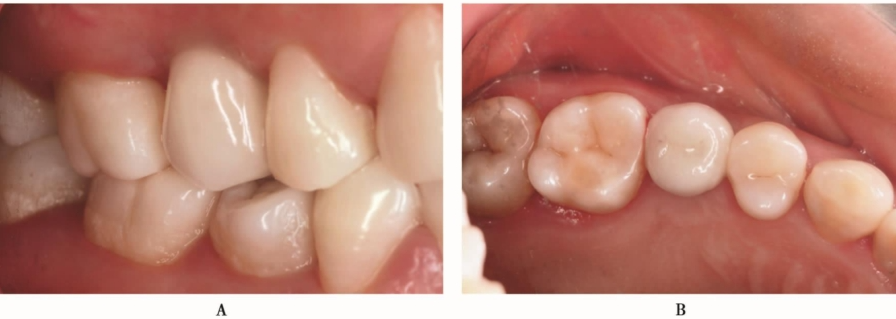

种植体植入后3个月,种植体周围骨结构良好,可以进行上部结构修复(图28)。完成上部结构修复(图29)

图29 完成上部冠修复A.颊面观;B.𬌗面观